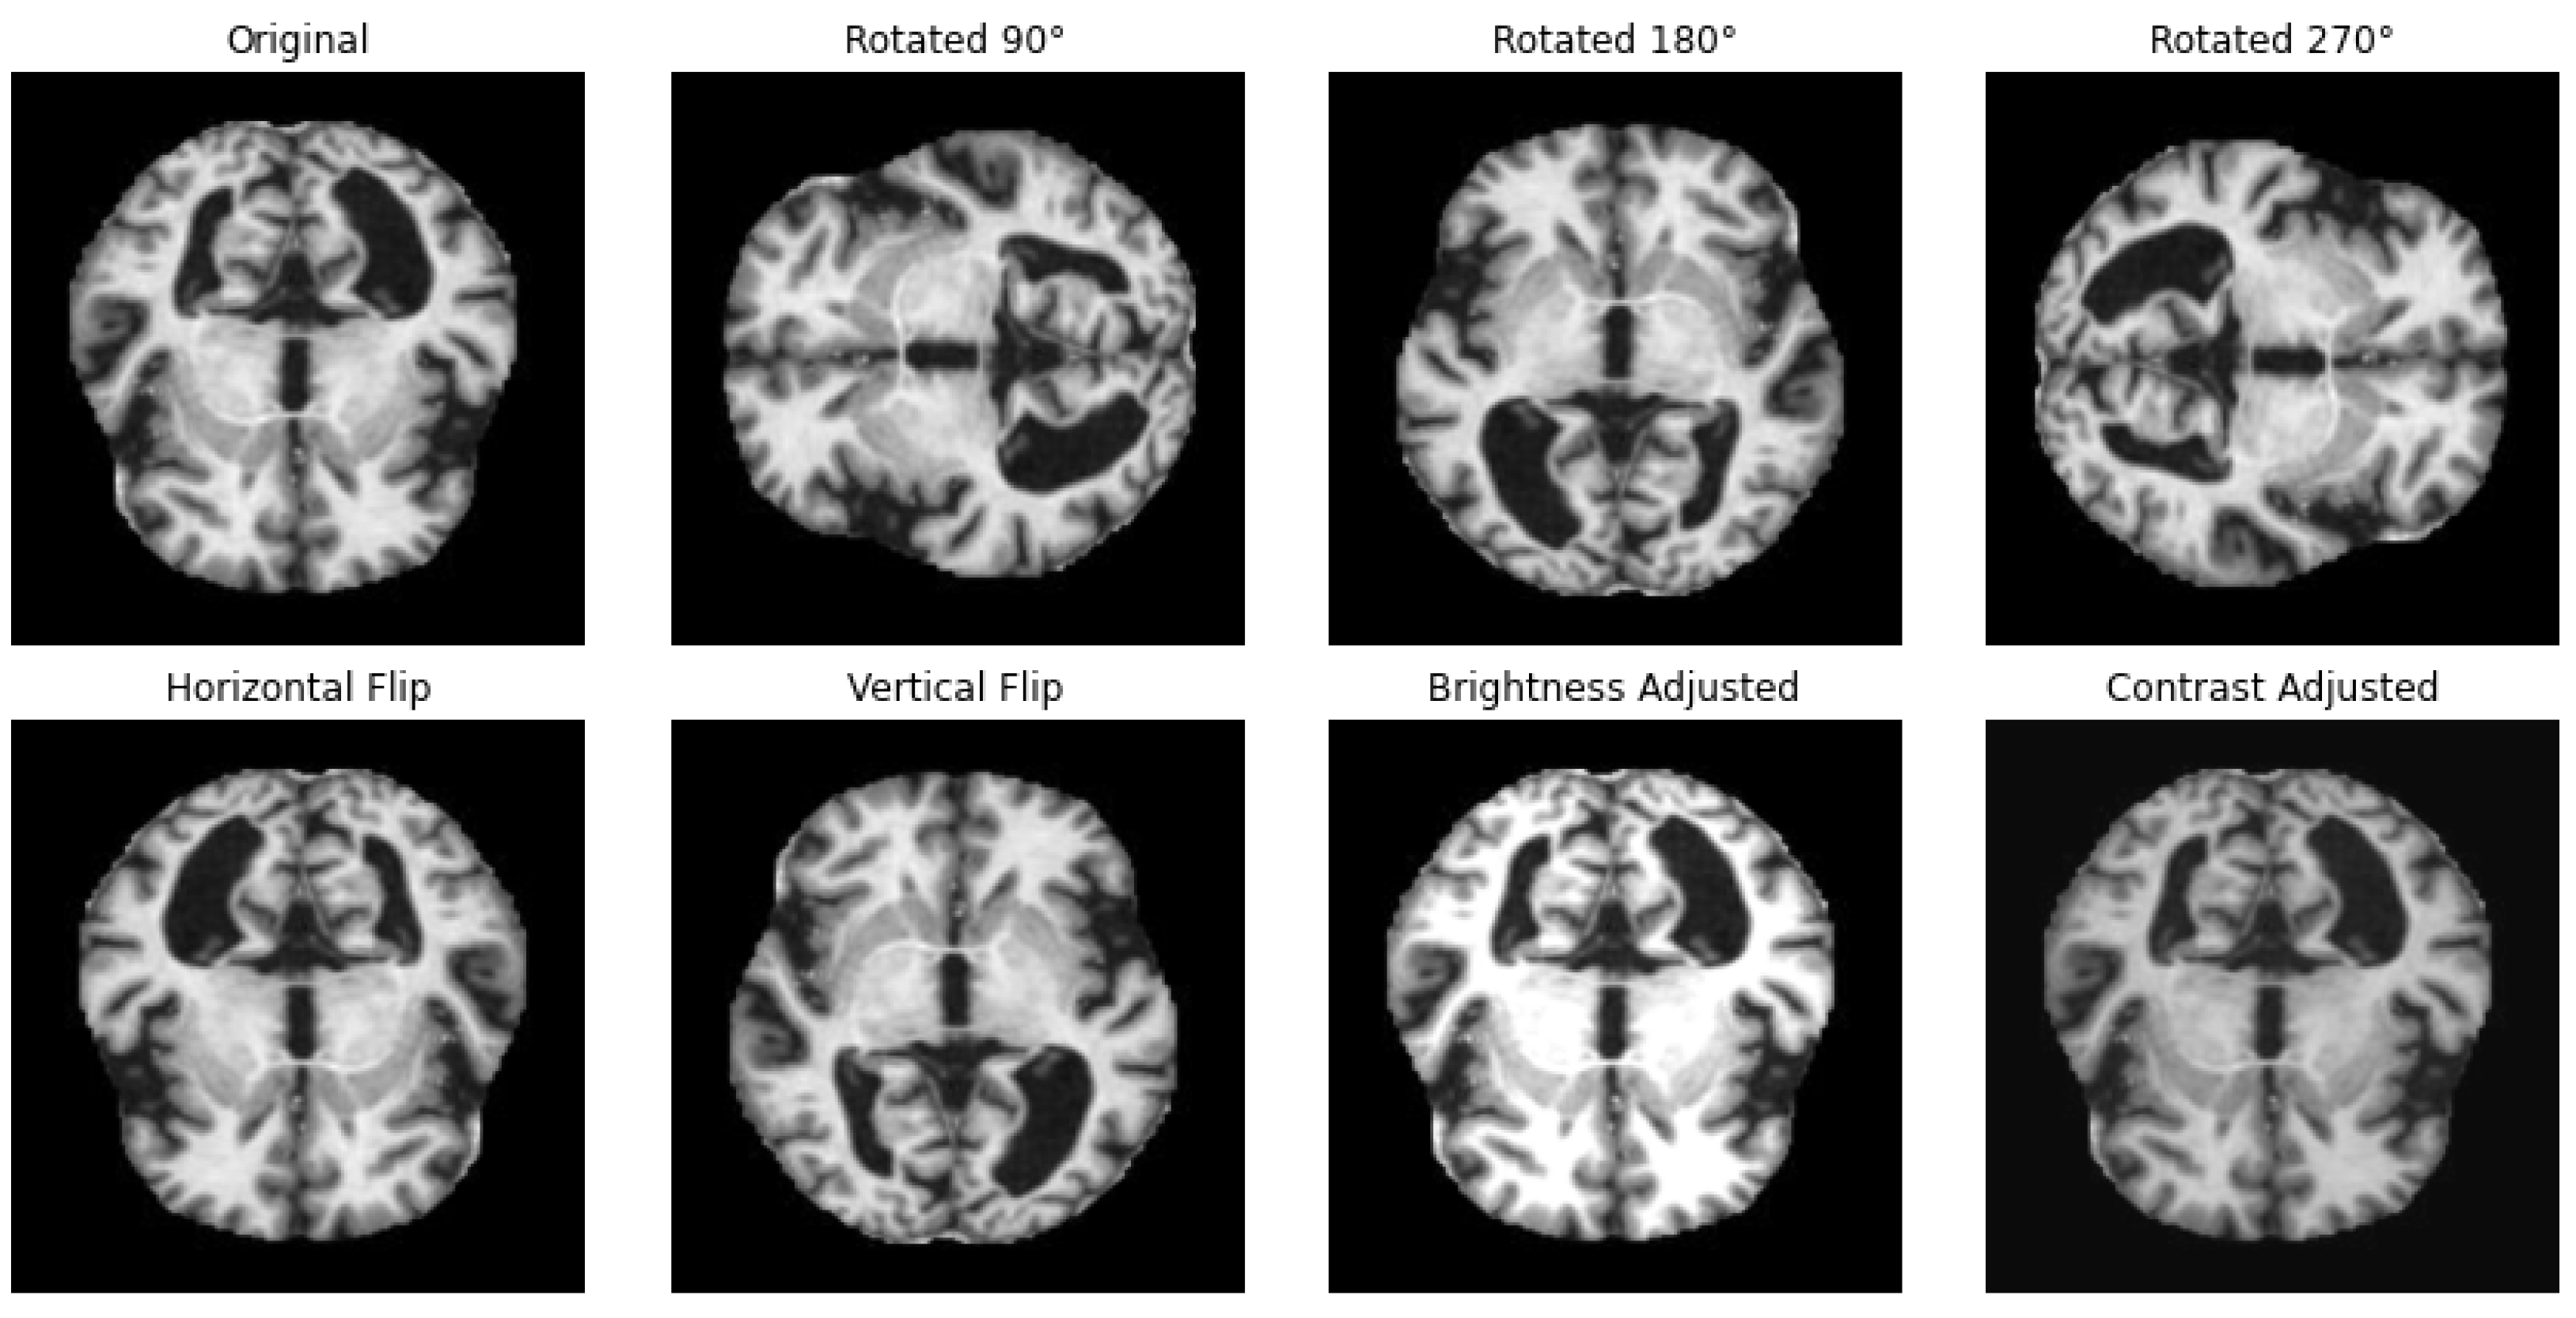

One way to artificially expand the amount and complexity of current data is through data augmentation [53]. To give developers access to more representative training data, data augmentation techniques have been used to increase the size of training sets [54,55]. In this study, we have applied different techniques for data augmentation to enhance the diversity of the datasets and to achieve a balanced distribution of classes, as in the example illustrated in Figure 2. The augmentation methods that we have employed include rotation, horizontal and vertical flipping, and other transformations to simulate different perspectives and conditions with the parameters summarized in Table 2.

Figure 2.

Illustration of applied data augmentation techniques.

Data augmentation parameters.